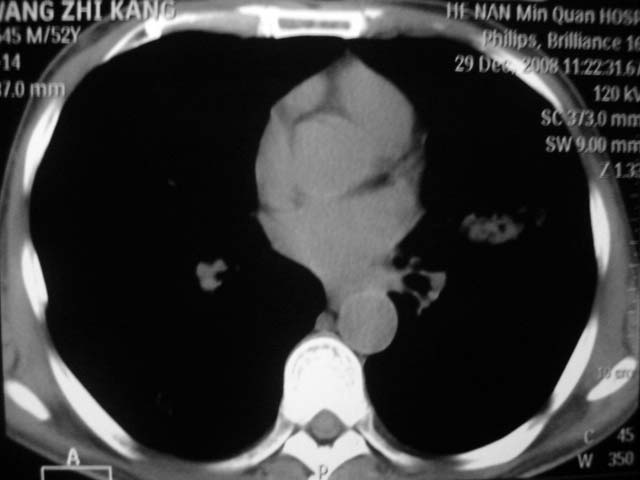

男,52岁,发热2月,糖尿病史。

抗结核治疗irpz方案,血糖未治疗,空腹15.9左右。症状无好转,左胸痛。

复查ct

2、双肺见多发片状及结节状高密度影,大多数病灶中心均见“空泡征”。

3、纵隔内淋巴结肿大。

结果:两肺继发性肺结核并曲霉菌感染。